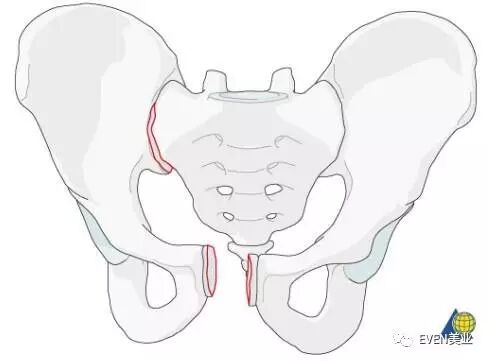

恥骨の病状の中には、骨折、股関節の病状および恥骨結合の拡張性が含まれる。 恥骨とは何ですか? 恥骨 としても知られている 恥骨 は、 腸骨 を構成する3つの骨部分の1つです。 腸骨の他の2つの部分は 腸骨 と 坐骨 です。 iliacoの骨は何ですか?恥骨骨折になってしまう3つの原因 恥骨を骨折してしまう原因は主に疲労骨折、打撲や転倒による衝撃、骨粗鬆症の3つがあげられます。 疲労骨折 恥骨骨折で最も多い原因が疲労によるものです。Mar 08, 16恥骨に関するトラブルとして、まずは骨折が挙げられます。 恥骨骨折の原因 恥骨骨折の原因として多いのは、 ・自動車事故 ・高所からの落下 の2つが多くみられます。 これらの骨折の場合は、恥骨だけでなく動脈や内臓にまで被害が及び、内出血や内臓

Feb 07, 骨粗鬆症による骨強度 (骨密度と骨質) の低下が原因となり, 軽微な外力 (立位姿勢からの転倒か, それ以下の外力で歩行や寝返り等も含まれる) で生じる骨盤の骨折です なお, 骨盤は左右の寛骨 (腸骨, 坐骨, 恥骨) , 後方の仙骨と尾骨からなる閉鎖環状構造を3DCTでは左の恥骨骨折も認めています。 この症例は、後方骨盤輪の離開を認めておらず日本外傷学会分類のⅠaの骨盤骨折に相当します。 症例 50歳代 男性 交通外傷疲労骨折とは、「骨折」という名前こそ付いていますが、一回の大きな外力で発生するいわゆる通常の外傷性の骨折とは異なります。むしろ小さな弱い外力が繰 り返し加わることによって軽い損傷が治ることなく残っている状態をいいます。 恥骨→長

Jul 07, 16「腸骨翼骨折」「恥骨骨折」「坐骨骨折」を 安定型 、 「腸骨骨折」「仙骨骨折」「船長関節離開」を 不安定型 に分類しています。 ※安定型はズレにくく、不安定型はずれる可能性がある。 骨盤骨折の原因は?恥骨骨融解症(Pubic osteolysis以下PO)は恥骨部の疼痛・違和感にて発生し、X線にて恥骨に骨融解像を認め、特に悪性腫瘍との鑑別が問題となる疾患である。 今回、仙骨骨折後にPOを発症し歩行障害と原因不明の膀胱直腸障害を生じた症例のリハビリテーション亀裂骨折 (ひび)の症状、原因、診断・治療方法についてご紹介します。リハビリテーション科、整形外科に関連する亀裂骨折 (ひび)の治療なら病院・クリニック検索のホスピタにお任せ下さい。亀裂骨折 (ひび)の診察ができるおすすめの病院をご紹介できるのは「いまから」機能搭載のホスピタ